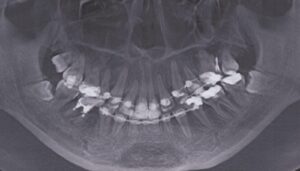

患者さんは14歳の中学2年性。臼歯部の虫歯治療で来院されました。

口腔内は、上下顎ともにごく僅かに叢生がありますが、臼歯部も1歯対2歯でちゃんと噛み合っていますし、

垂直被蓋、水平被蓋ともに正常であり、噛み合わせには特に問題があるようには思えません。

さて、叢生も少なく静的動的な歯の接触、つまり咬合が特に問題ない(むしろ平均以上)。

この患者さんは、主に上顎が優勢であり、上下歯列は理想的な位置より前に出てきてしまっています。

前方に出過ぎてしまった前歯を舌側へもって行くということは、同時に歯槽骨を改善されるわけですから、

ベースとなっている上顎骨がやや大きくても、歯を移動させることによって、カムフラージュすることになります。

骨格の位置のズレをこのように歯の移動によって補償することを、『デンタルコンペンセーション』といいます。

もし『デンタルコンペンセーション』の必要性の高い患者がいたとしたら、それは歯の凸凹とは関係なく、矯正治療の対象となるのです。